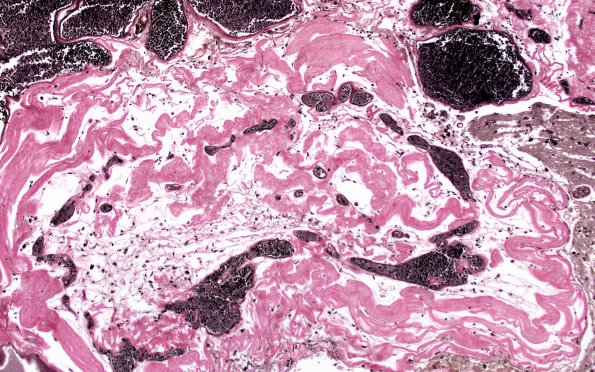

Washington University Experience | VASCULAR | Cavernous Angioma | 31E6 Cavernoma (Case 31) VVG 10X 5

Multiple images of the malformation stained for elastin. An elastin stain demonstrates the internal elastic lamina of arteries/arterioles and fails to stain the walls of the cavernoma. (elastin)